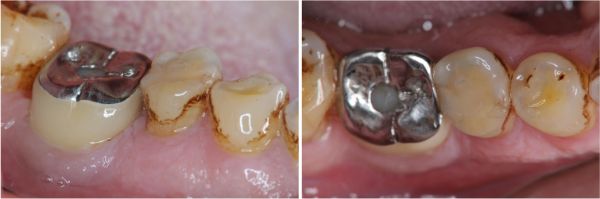

治療前#45蛀牙至牙髓

磨損與蛀牙,塞食物

術前、術後比較